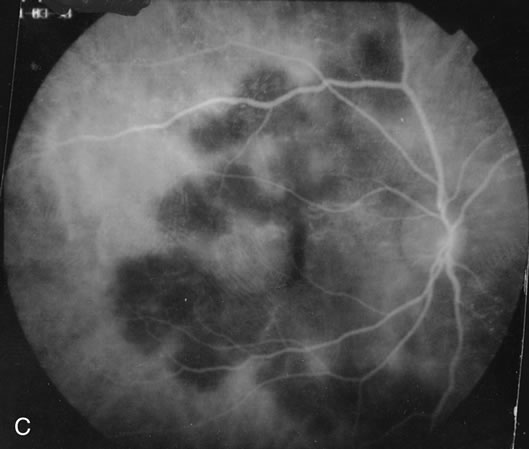

The classic findings in the acute cases are lesions of variable size that are hypofluorescent in the early phase of the fluorescein angiogram. In the late phases of the angiogram there is hyperfluorescence of the lesions. In the late phases, there also may be leakage from the disc as well, and there also may be staining of the retinal vessels because of the vasculitis. With resolution of the disease, there still may be a mottled pattern of fluorescence correlating with the areas of pigment clumping and pigment atrophy (Fig. 8).

Fig. 8. A. Early fundus angiogram showing hypofluorescence of the acute posterior multifocal placoid pigment epitheliopathy (APMPPE) lesions. B. Later stage of the angiogram showing staining of the APMPPE lesions.

Indocyanine Green

ICG angiography shows an absence of fluorescence in the early as well as in the late phases of the angiogram. This is consistent with the possibility that the disease is caused by a choroidal occlusive vasculitis. There may be more lesions than seen ophthalmoscopically or by fluorescein angiography. In addition, there may be the development of new lesions in the first few weeks that can be seen by indocyanine green that cannot be seen by fundoscopy.35 This appears to imply that the disease is first a choroidal vasculitis, and in the more severe cases it can then affect the overlying retinal pigment epithelium and outer retina.